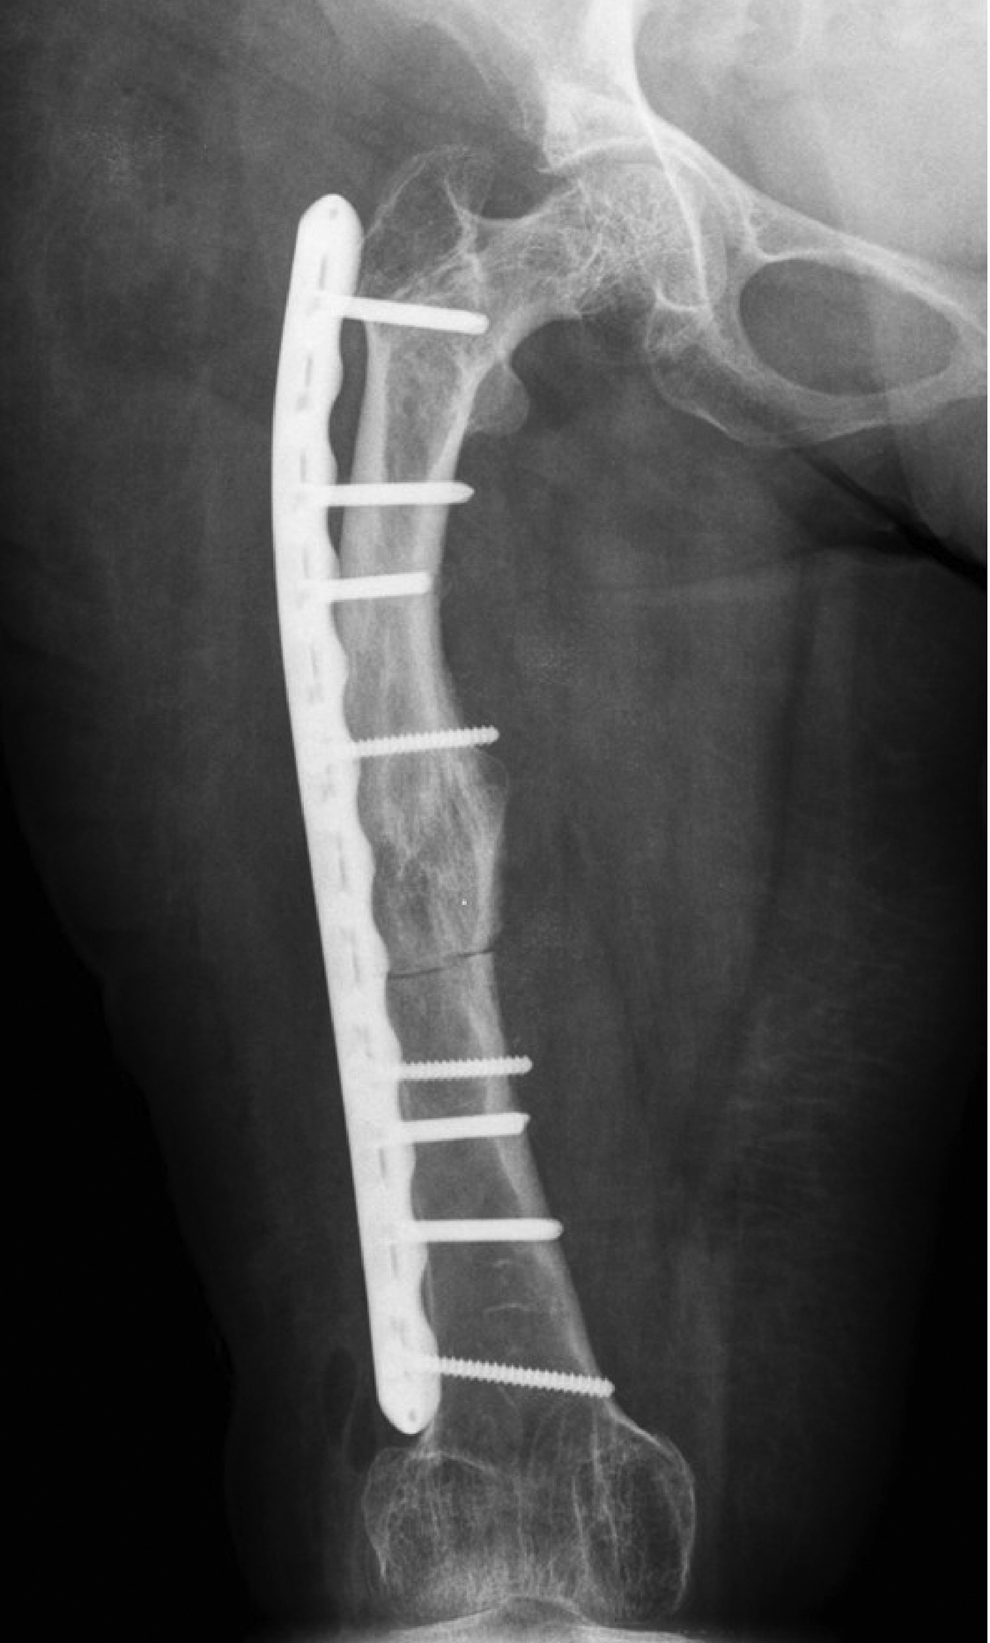

Во время этого вмешательства были выполнены открытая репозиция отломков с сохранением предсуществующей формы правой бедренной кости и компрессионный остеосинтез пластиной с блокированием. Для деконцентрации напряжения по краям фиксатора в надмыщелковой зоне бедренной кости использован неблокируемый бикортикальный винт 4,5 мм, а в проксимальном отделе блокируемый винт был введен по касательной, кпереди от дуги Адамса. Удаление имплантатов не планировалось. После консолидации кости на этом уровне в сроки 10 месяцев у пациентки восстановилась опороспособность конечности. Однако произошел периимплантный низкоэнергетический подвертельный перелом бедренной кости при падении на правый бок 01.01.2019 г.

При госпитализации пациентки в отделение травматологи ортопедии МОНИКИ установлено, что линия перелома проходила косо-поперечно через канал второго винта (рис. 3), на котором концентрировались изгибающие нагрузки из-за сохраняющейся варусной деформации проксимального отдела бедренной кости. К сожалению, проксимальный винт не обеспечил деконцентрацию нагрузки, что привело к усталостным изменениям кости и последующему перелому.

Рисунок 3. Рентгенограммы пациентки с периимплантным переломом бедренной кости.

В связи с этим после стационарного обследования 29 января 2019 г. была выполнена операция — удаление винтов и пластины из правого бедра, экономная адаптирующая резекция на уровне периимплантного перелома, корригирующая деваризация и компрессионный остеосинтез блокируемой пластиной. Для остеосинтеза использовалась «перевернутая» контрлатеральная дистальная бедренная пластина в режиме динамической компрессии двумя кортикальными винтами. Для деконцентрации напряжения был использован монокортикальный дистальный винт. С учетом сниженной минеральной плотности кости количество винтов, введенных в каждый отломок, было больше, чем при остеосинтезе бедренной кости без остеопороза (рис. 4).

Рисунок 4. Рентгенограммы пациентки после операции удаления имплантатов, корригирующей остеотомии проксимального отдела правой бедренной кости и остеосинтеза блокируемой пластиной.